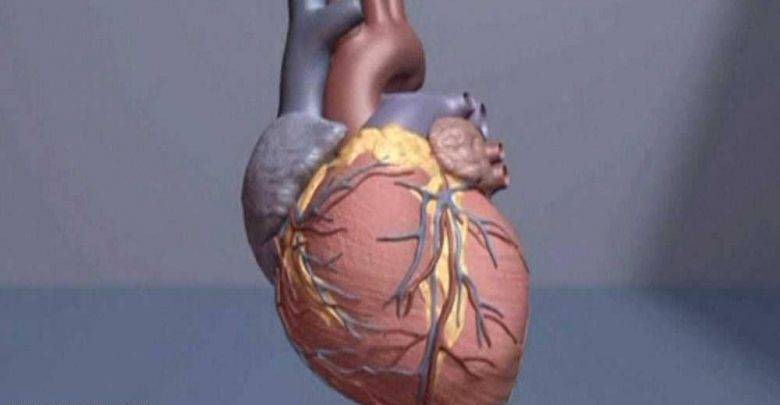

دراسة تكشف عن مسببات غذائية لأمراض القلب القاتلة

أمراض القلب من أكبر مسببات الوفيات حول العالم، لكن يمكن تفادي الإصابة بها عبر التركيز على نظام غذائي معين وفق دراسة حديثة.